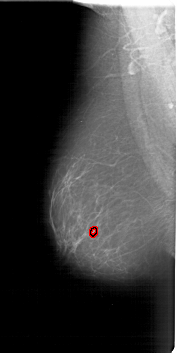

FILE: A_1800_1.LEFT_MLO.OVERLAY

TOTAL_ABNORMALITIES 1

ABNORMALITY 1

LESION_TYPE MASS SHAPE LOBULATED MARGINS ILL_DEFINED

ASSESSMENT 4

SUBTLETY 3

PATHOLOGY BENIGN

TOTAL_OUTLINES 1

BOUNDARY